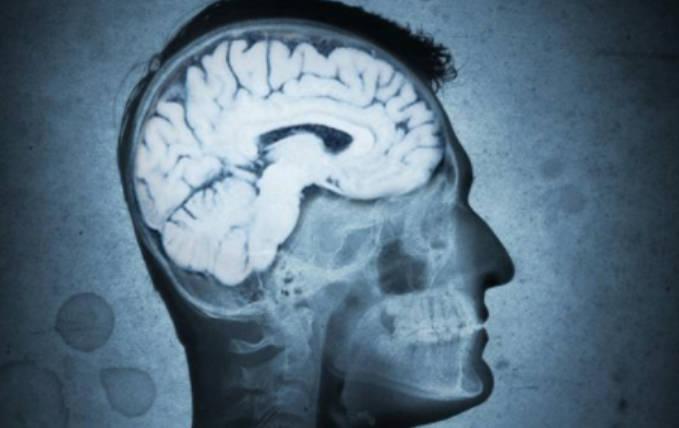

一夜不睡覺會對大腦造成很大的損傷,現在很多人互相熬夜當成是很平常的一種生活習慣,甚至是一個晚上都不睡覺,利用晚上睡覺的時間打游戲,加班或者是刷劇,具體是一些比較年輕的人覺得一晚上不睡覺,并不礙事,這種想法是非常錯誤的,近段時間就有研究,表明一個晚上不睡覺,大腦在第二天就會快速變老,思想性的研究是在近期發表于國際權威期刊的《神經科學雜志》,由德國神經科學與醫學研究所科研團隊完成的一項新的研究。

熬夜很傷腦

在這項研究中,對134名平均年齡在25.3歲的參試者進行了睡眠數據的分析,在研究過程中,會通過核磁共振掃描參試者的大腦,再根據大腦組織的特征等數據判斷大腦的年齡,經過研究證明,一夜不睡的參試者在第二天檢查時大腦比之前檢查的要老1~2歲。

根據研究,一個晚上不睡對大腦造成的損傷若在第二天恢復正常睡眠之后,通過掃描大腦的年齡,就會重新恢復到正常的狀態,通過研究表明,不管是任何原因導致的一夜不睡對大腦造成的損傷,通過第2天補覺,也可以適當的逆轉,但是并不代表著人可以任意熬夜,如果經常熬夜會對大腦造成非常嚴重的損傷。

如果長時間晚上不睡,大腦會自動形成一種默認的模式,每到晚上就會過度活躍,但是其實人的大腦前額葉皮層與頂葉皮層之間的聯系會發生減弱,這種情況在老年人身上是很常見的,根據研究結果證明一個晚上不睡覺,會使人的腦部神經元特異性稀醇化酶呈現上升趨勢,長期缺乏睡眠,會使人很容易患上阿爾茲海默癥、帕金森病或者多發性硬化癥。